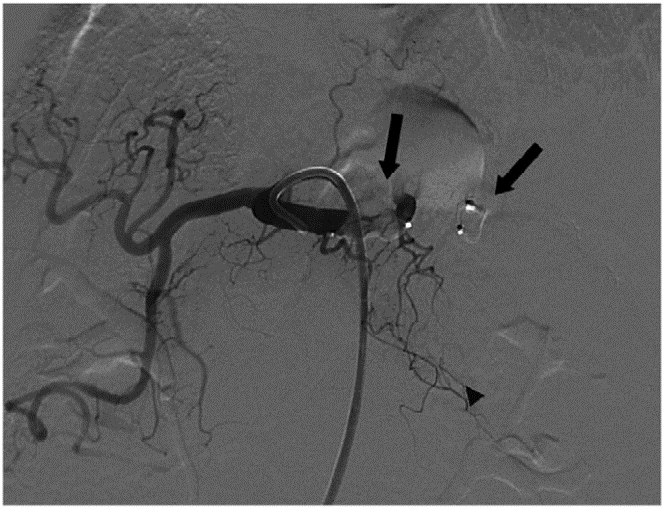

陈仁彪教授:使用Amplatzer Vascular Plug 4(AVP 4)治疗脾门处脾动脉瘤

刘军乐教授:AVP在脾动脉瘤中的应用

刘超教授:AVP Ⅱ血管塞治疗腹腔干假性动脉瘤

Amplatzer血管塞病例集锦 — 内脏动脉瘤

图片

使用AVP对于脾动脉瘤近端远端进行栓塞